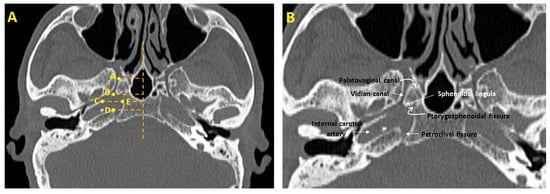

| Parameters | Definitions of Landmarks (Figure 1) |

|---|---|

| FL length(mm) | The distance between the posterior end of the VC opening into the FL and the petrous apex of the temporal bone (B–D). |

| FL width (mm) | The distance between the temporal bone’s petrous apex and the sphenoid bone’s corpus (C–E). |

| VC length (mm) | The distance between the anterior end of the VC opening into the pterygopalatine fossa and the posterior end of the VC opening into the FL (A,B). |

| VC—pterygosphenoidal fissure angle (°) | The angle formed between the VC and the oblique line drawn from the pterygosphenoidal fissure. |

| VC—palatovaginal canal angle (°) | The angle formed between the VC and the oblique line drawn from the palatovaginal canal. |